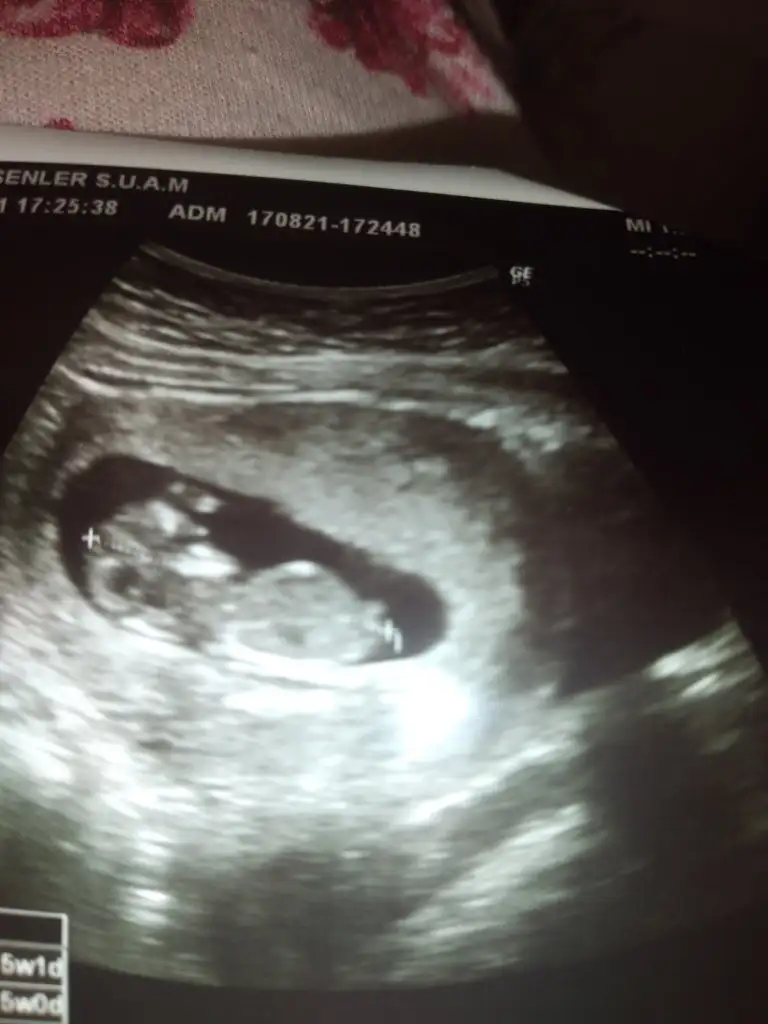

Erkek ve kız için 11 + 12+ yada 13 hafta usg görüntüsü olmalı açıklamalar asagıda yazıyorrabbim herkesin gönlüne göre nasip etsin inşallah .. ecmain

[/B]Eki Görüntüle 473828 gordugunuz gibi ust taraftaki simgedende anlasildigi gibi eger cikinti paralel ise kiz

yok 30°lik bir aciyla yukari dogru bakiyorsa %99 oglunuz olacak demektir simdi bi kac ornek resimler daha koyacagim kiziminkide dahil

Eki Görüntüle 473831 simdi burada cikintilara bakin eger bel popo cizgisine paralel ise kiz

yok 30 derecelik bir aciyla yukari bakiyorsa erkek

yabancilarin hepsi biliyor bunu biz neden eksik kalalim gayet bilimsel simdi ellerinde11 12 13 ultrason fotografi olanlar alsin hemen baksin yada koyalim buraya yorumlayalim